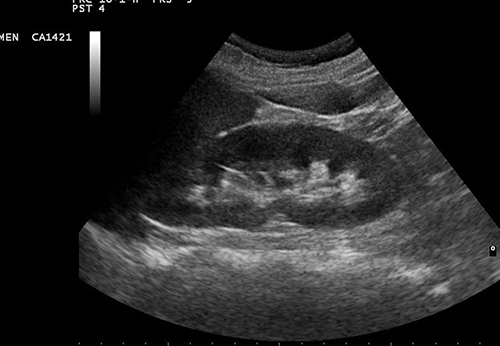

Новое исследование показало, что почки могут быть восстановлены до трансплантации путем доставки клеточной терапии непосредственно к органу.

Команда, возглавляемая исследователем из Университета Ньюкасла, доктором Эмили Томпсон, первой обнаружила, что новая методика, называемая перфузией Normothermic, в сочетании со стволовыми клетками, может использоваться для улучшения функции «маргинальных» почек, которые могут стать проблемными после трансплантации, повышая шансы на необходимость дополнительной пересадки.

Обработка почек стволовыми клетками продемонстрировала улучшение функций органа. В частности, улучшился кровоток, увеличилась выработка мочи.